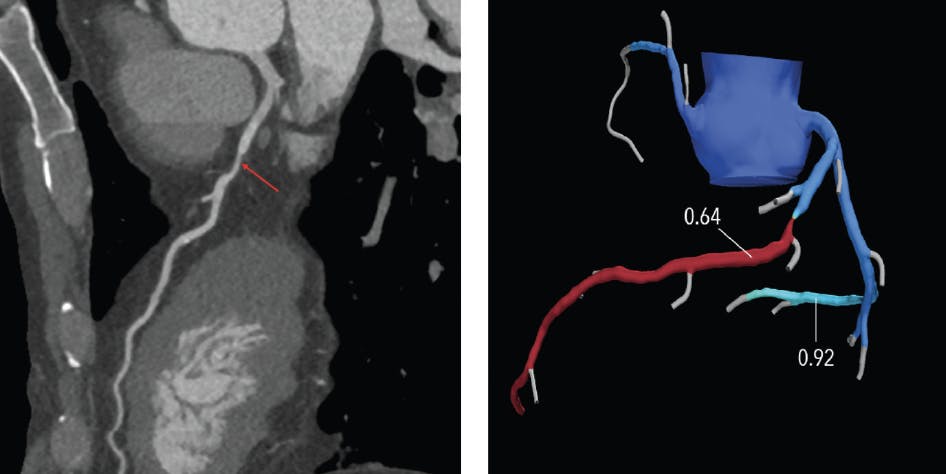

FFRCT is the alternative method to obtain lesion-specific ischemia assessment when deemed necessary across any stenotic lesion within the coronary tree from a coronary CTA (Figure 1). Although invasive FFR is the gold standard, it is acquired only during the invasive procedure and only detects the pressure gradient within the targeted vessel, as defined by the interventionalist. Furthermore, invasive FFR is not regularly assessed in clinical practice due to the extended time required for the procedure, greater radiation exposure, and the requirement for the administration of adenosine. FFRCT, on the other hand, can be added to coronary CTA for lesion-specific physiologic assessment without the need for a separate procedure, resulting in no additional radiation or contrast administration.

Figure 1. FFRCT of the left anterior descending artery indicating a flow-limiting lesion.